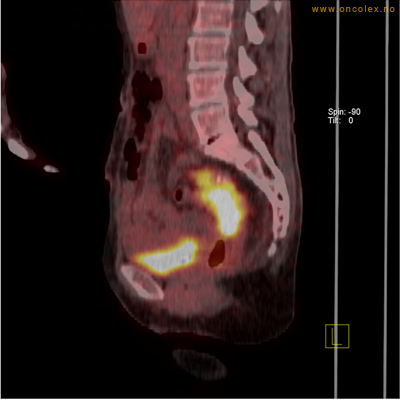

PET/CT (PET: Positron Emisjons Tomografi/ CT: Computer Tomografi) er en avansert nukleærmedisinsk bildetakingsmetode. Metoden er et godt dokumentert, veletablert og svært nyttig verktøy i bildediagnostikk ved kreft. Et PET-kamera gir tredimensjonale bilder av hele kroppen. Integrert CT gjør at informasjonen fra PET blir lokalisert anatomisk nøyaktig.

Kort beskrivelse av undersøkelsen

Gjennom en nål (plastkanyle) i en blodåre i armen vil du få et radioaktivt stoff. Det mest vanlige er radioaktivt druesukker (18F-FDG). Stråling fra det radioaktive stoffet registreres i PET-skanneren og viser hvordan dette stoffet fordeler seg i kroppen. Det normale opptaket av det radioaktive stoffet vil være endret ved sykdomsprosesser. Celler med høyt stoffskite, som for eksempel kreftceller, har økt opptak av sukker. Ved undersøkelsen kan man dermed ofte se større opptak av det radioaktive sporstoffet i kreftsvulster.  Siden CT tas samtidig, kan PET og CT bildene legges sammen og vise nøyaktig hvor i kroppen det økte opptaket er.

Eksempler på funn

Vev som tar opp mer radioaktivt stoff, synes som hvite områder som lyser opp mer i forhold til annet vev som tar opp mindre sukker.